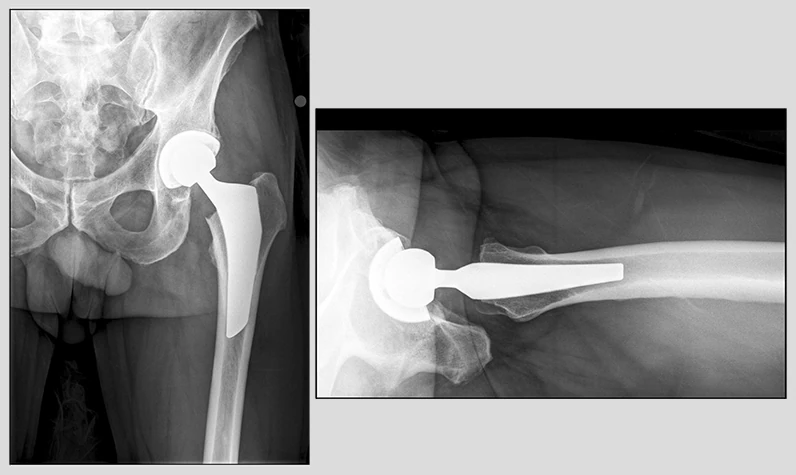

Эндопротезирование тазобедренного сустава

Эндопротезирование тазобедренного сустава является одной из наиболее эффективных и распространенных хирургических операций, направленных на восстановление функций сустава и улучшение качества жизни пациентов. При проведении данной операции поврежденные или заболевшие части сустава заменяются искусственными компонентами, изготовленными из металла, керамики или пластика. Целью операции является устранение боли, восстановление мобильности и нормализация двигательной активности пациента. Современные технологии и материалы, используемые в эндопротезировании, позволяют восстановить суставы даже в самых сложных и запущенных случаях, предлагая пациентам возможность возвращения к полноценной жизни. Операция может быть рекомендована пациентам с различными заболеваниями и повреждениями суставов, включая артроз, ревматоидный артрит и переломы шейки бедра. Показания к операции Замена тазобедренного сустава рекомендуется в случаях, когда консервативное лечение не приносит желаемого эффекта, и когда

Эндопротезирование тазобедренного сустава является одной из наиболее эффективных и распространенных хирургических операций, направленных на восстановление функций сустава и улучшение качества жизни пациентов. При проведении данной операции поврежденные или заболевшие части сустава заменяются искусственными компонентами, изготовленными из металла, керамики или пластика. Целью операции является устранение боли, восстановление мобильности и нормализация двигательной активности пациента.

Современные технологии и материалы, используемые в эндопротезировании, позволяют восстановить суставы даже в самых сложных и запущенных случаях, предлагая пациентам возможность возвращения к полноценной жизни. Операция может быть рекомендована пациентам с различными заболеваниями и повреждениями суставов, включая артроз, ревматоидный артрит и переломы шейки бедра.

Затем проводится установка компонентов эндопротеза. Головка и шейка эндопротеза устанавливаются в бедренный канал, а тазобедренная чашка эндопротеза устанавливается в таз. Фиксация эндопротеза может быть выполнена с помощью специального костного цемента или без его использования, в зависимости от выбранной технологии и типа эндопротеза.